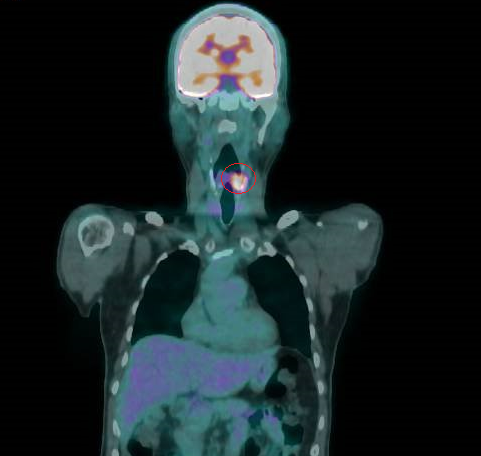

▲正子攝影顯示曾先生的下咽癌再度復發(紅圈處)。(圖╱彰化醫院提供)

衛福部彰化醫院耳鼻喉科主任許嘉方表示,曾先生3年前喉嚨疼痛不癒,經內視鏡、電腦斷層等檢查發現,他的左下咽處有個2公分的腫瘤,切片確定為惡性,是第2期癌症,不進行切除手術,採放射及化學療法,治療後腫瘤消失。

許嘉方說,過了3年曾先生復發了,同位置的腫瘤2.1公分,也是2期,經評估不適宜再進行放療及化療,只得進行全喉切除,連同聲帶一併切除,在頸部開個永久氣切孔呼吸,讓口腔只用於進食,也就是飲食及呼吸分開,至於聲音部分,使用人工發聲器。